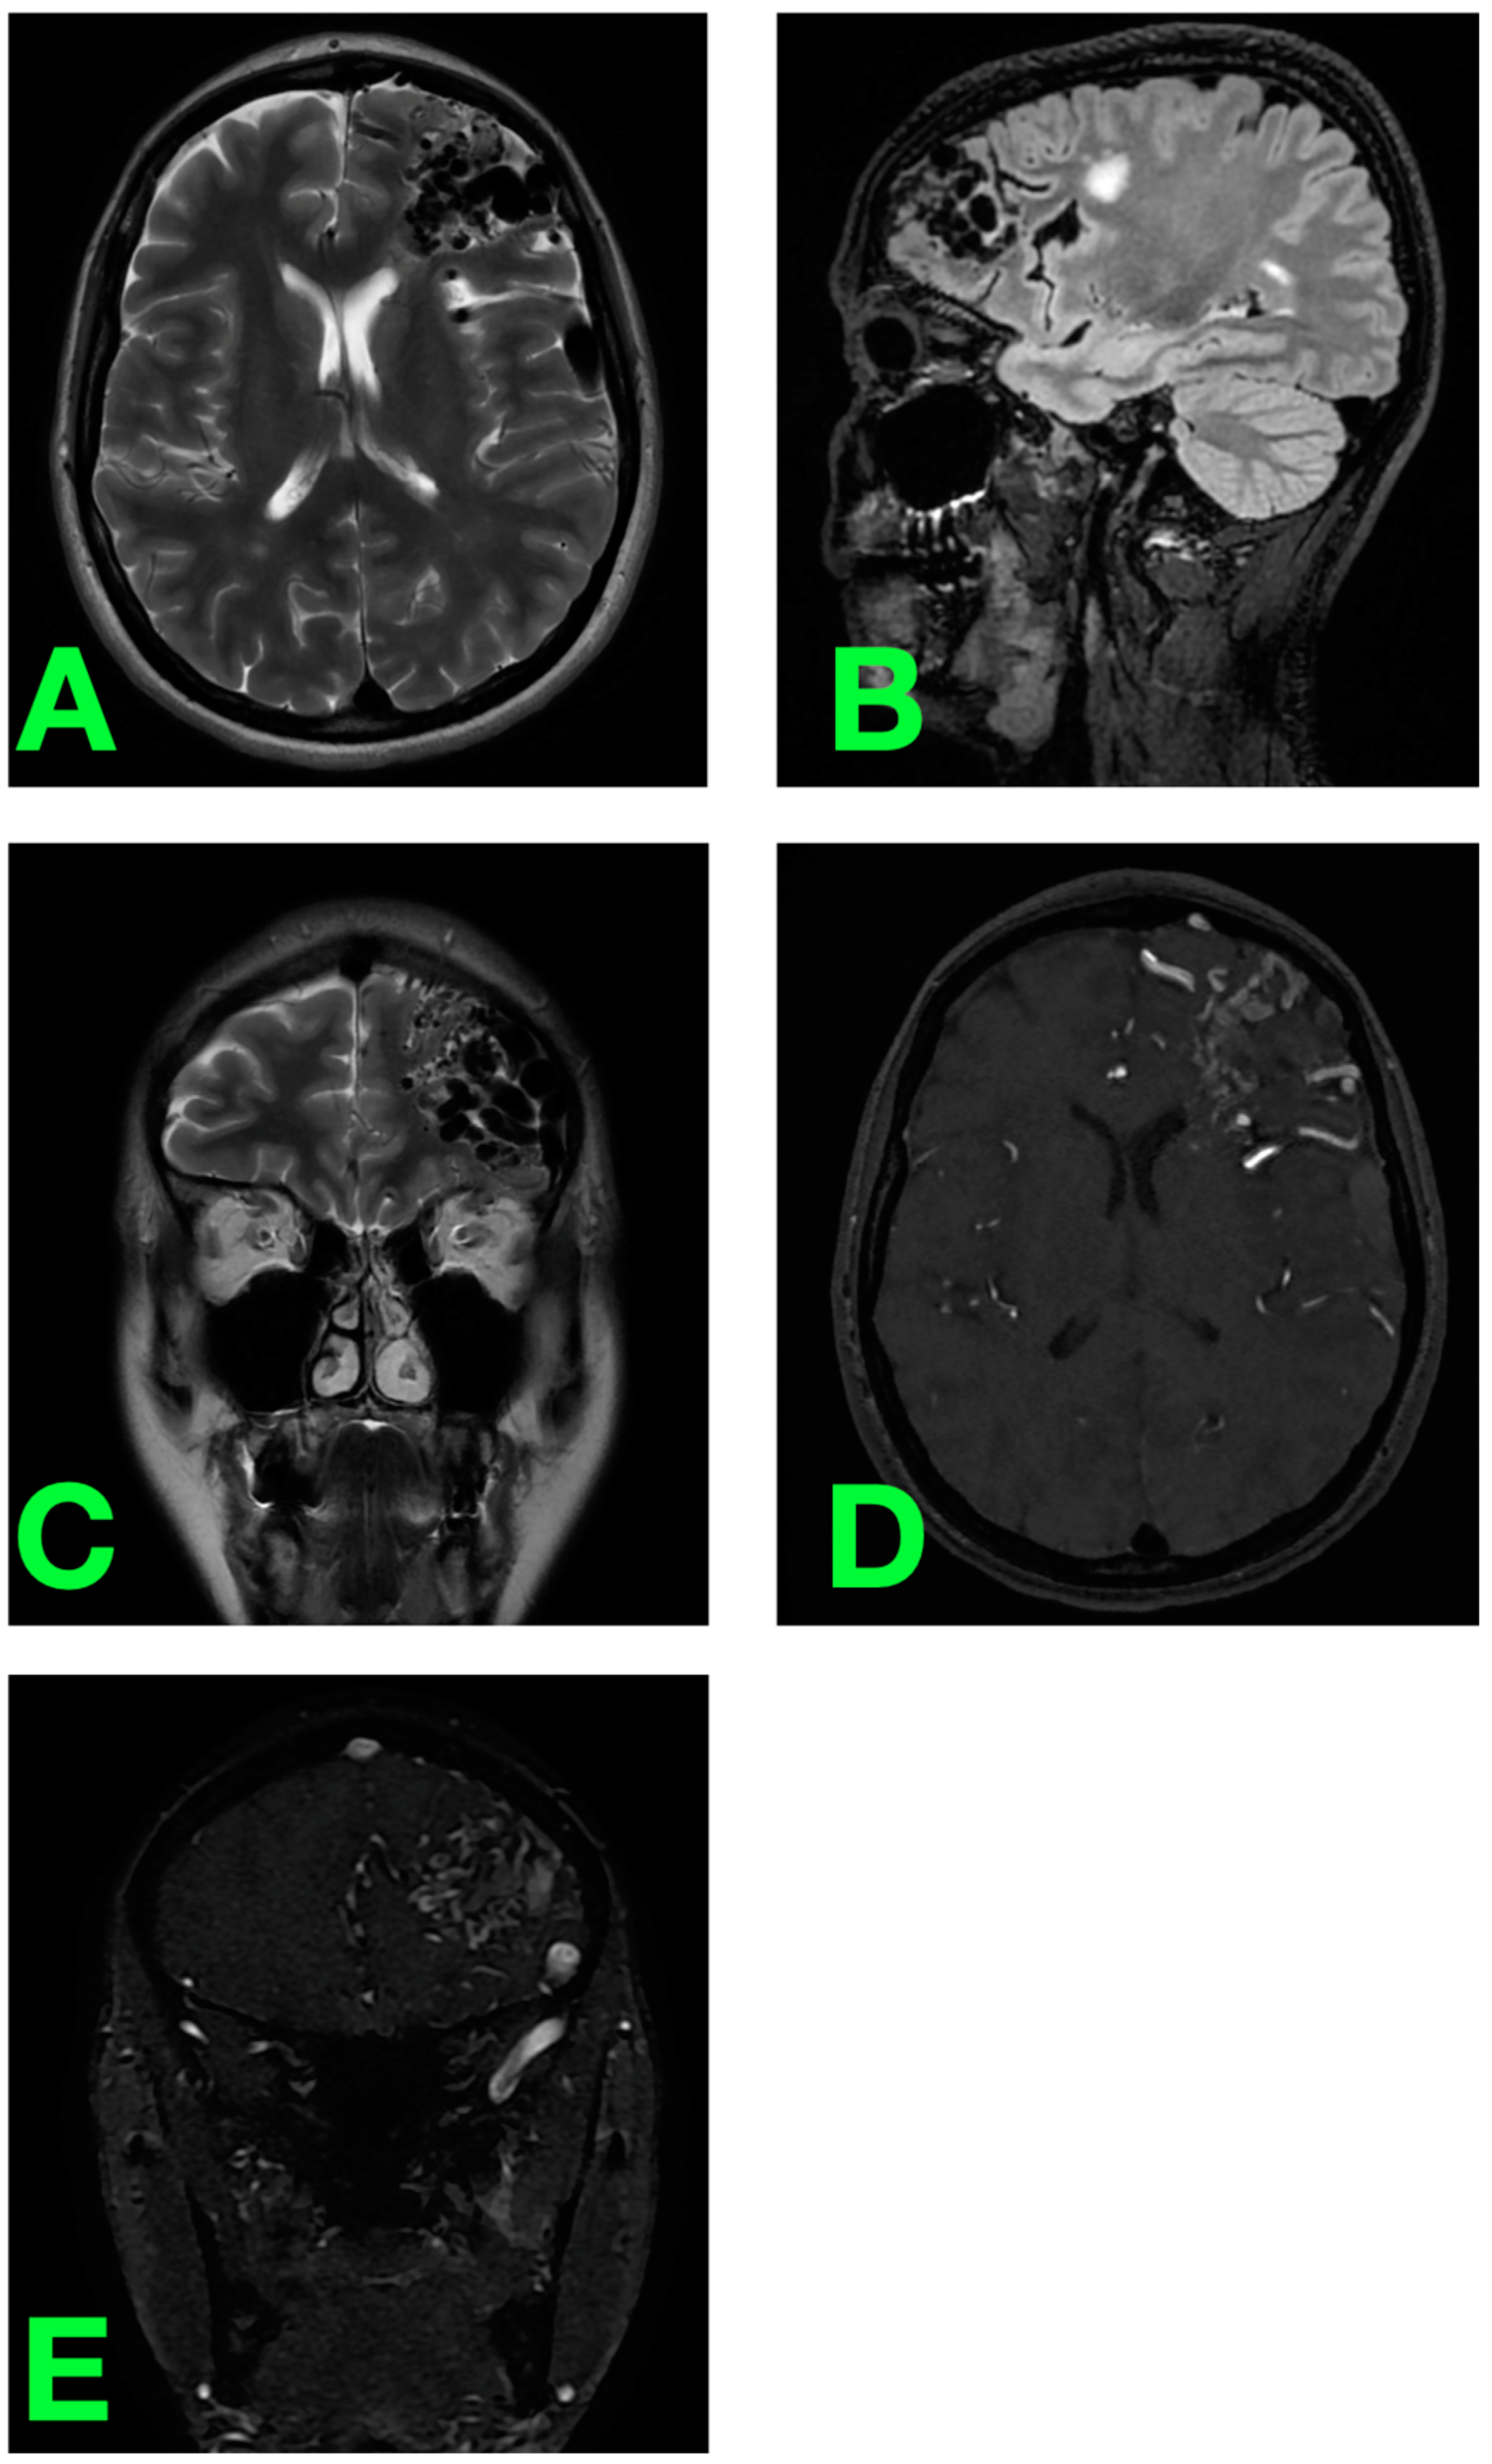

2.2. Diagnostic Workup

2.3. Clinical Impression and Decision Making